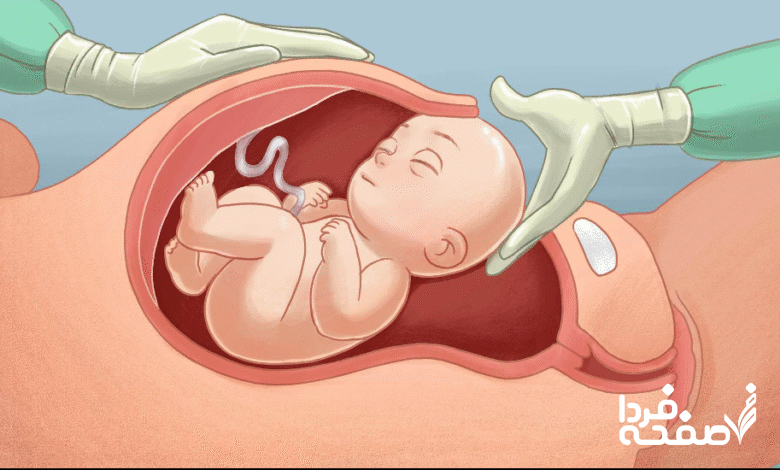

هشدار درباره سزارینهای تقویمی؛ تاریخ تولد نباید سلیقهای باشد!

معاون درمان دانشگاه علوم پزشکی همدان با هشدار درباره افزایش سزارینهای تقویمی تأکید کرد: تاریخ تولد نباید به دلایل شخصی یا اعتقادی، سلامت مادر و نوزاد را به خطر بیندازد.

غلامرضا کلوندی صبح امروز در جمع خبرنگاران در سالن جلسات معاونت طی ابلاغیهای بر لزوم ثبت دقیق، بهموقع و واقعی موالید و مقابله جدی با پدیده سزارینهای انتخابی تقویمی تأکید کرد و گفت: برخی خانوادهها به دلایل شخصی یا اعتقادی، تاریخ تولد فرزند خود را با روزهای خاص هماهنگ میکنند، اما این موضوع نباید منجر به انجام زایمانهای غیرعلمی و سزارینهای غیرضروری شود.

وی بیان کرد: تیمهای نظارتی دانشگاه با حضور میدانی در بیمارستانها، عملکرد مراکز درمانی، پزشکان و تیمهای زایمانی را در زمینه رعایت بخشنامههای وزارت بهداشت و میزان سزارینهای انجامشده مورد بررسی دقیق قرار خواهند داد.

معاون درمان دانشگاه علوم پزشکی همدان با اشاره به ماده ۵۰ قانون حمایت از خانواده و جوانی جمعیت، بر اهمیت حفظ استانداردهای خدمات بارداری و زایمان و پرهیز از مداخلات بیدلیل در فرآیند زایمان تأکید کرد و افزود: نظارتها بهویژه در بیمارستانهایی که آمار سزارین بالا دارند، با حساسیت بیشتری انجام میشود.

وی در پایان خاطرنشان کرد: هدف اصلی ما، سلامت مادر و نوزاد، احترام به اصول علمی پزشکی و جلوگیری از تبدیل تاریخ تولد به مسئلهای سلیقهای بوده و سیاست ما حمایت از زایمان طبیعی ایمن و مقابله با سزارینهای بیمورد است.